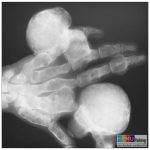

Xương đặc đốm (Osteopoikilosis) là một loạn sản xơ xương, đặc trưng bởi nhiều đảo xương (Enostosis) lành tính. Là một bệnh lành tính di truyền hiếm gặp, thường tình cờ phát hiện trên phim chụp X-Quang thường quy. Những đảo xương trong xương đặc đốm phát triển trong thời thơ ấu và không thoái triển do đó tổn thương gặp ở tất cả nhóm tuổi, không có ưu thế về giới…